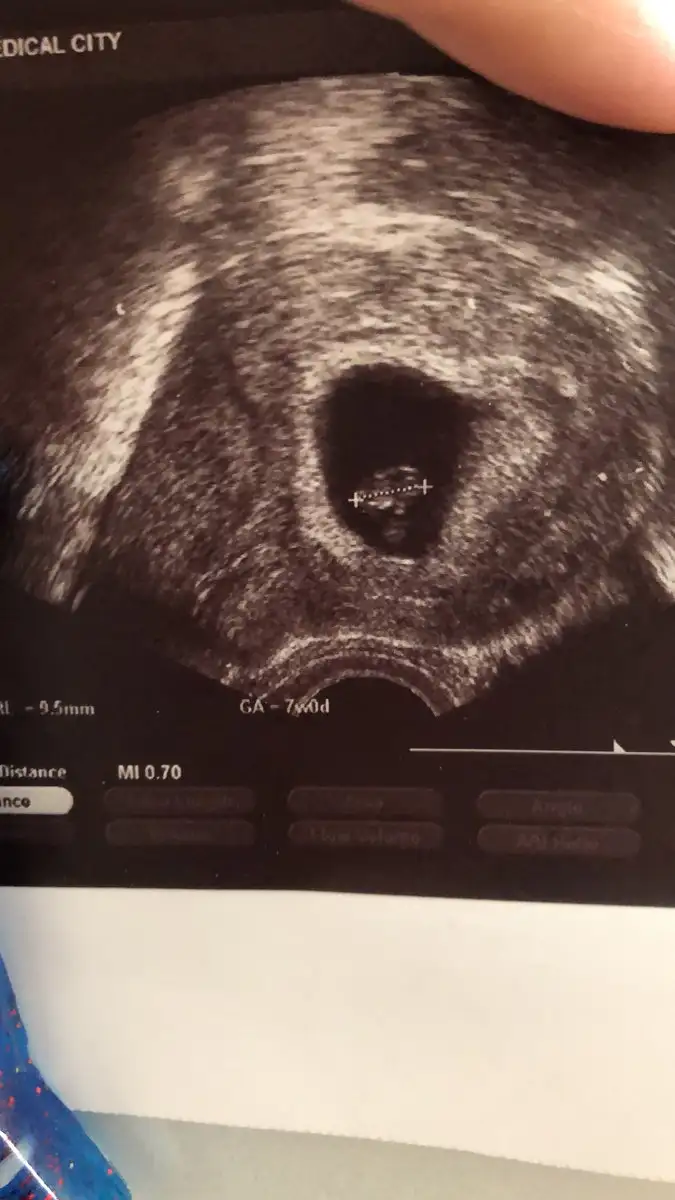

Merhaba. Ben de tahmin konusunda birşey sormak istiyorum. Ben hamileliği öğrendiğimde iki farklı doktora gittim. İkisi de karnımdan baktıklarında ultrasonu sol kasığımın üstüne tutarak keseyi incelediler. Yani sol elimin olduğu taraf. Buna göre kız mı erkek mi sizce? Sonra vajinal da bakıldı. Şimdi görüntü paylaşsam iyice kafam karışacak. En iyisi böyle anlatayım dedim.